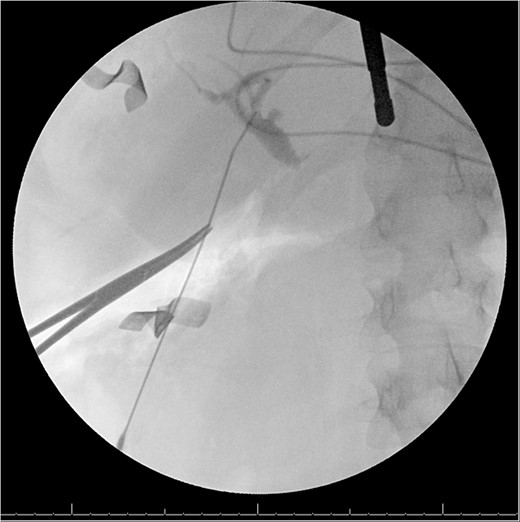

A 49-year-old female with a history of ADPKD and multiple liver cysts, 13-months status post subtotal cholecystectomy, endoscopic retrograde cholangiopancreatography with biliary sphincterotomy and balloon stone extraction, presented to the emergency department with fever and a 4-day history of discomfort in the right upper quadrant. At the time of the initial cholecystectomy, total cholecystectomy could not be performed due to extensive adhesions, and subtotal cholecystectomy with complete evacuation of the stones was done instead. Magnetic resonance cholangiopancreatography (MRCP) done at that time showed a dilated common bile duct (CBD) to 1.5 cm, intra and extrahepatic biliary dilatation, multiple liver cysts measuring up to 2 cm, and multiple stones in the CBD, including at the level of the ampulla (Fig. 1). Computerized tomography scan at the time of the second admission showed acute cholecystitis and she had mildly elevated transaminases, but there was no evidence of cholestasis or pancreatitis. MRCP showed minor proximal intrahepatic biliary dilation and cholelithiasis but no duct calculi (Figs 2–4). A laparoscopic cholecystectomy was attempted with extensive adhesiolysis between the gallbladder and surrounding omentum and mesocolon, but the cystic duct could not be isolated, and ultimately the cased was converted to open. While removing the gallbladder in a top-down fashion, a small bile leak was identified right at the closed end of the gallbladder remnant, where the bile duct was adhered to the gallbladder wall. Intraoperative cholangiogram was obtained through a small perforation in a right posterior bile duct at the site of attachment, which showed right posterior, right anterior and left hepatic ducts of equal size converged at a trifurcation (Fig. 5). The duct was repaired over a T-tube and observed throughout the rest of the case and no bile leak was identified. The gallbladder was opened along its lateral edge, revealing a hugely dilated cystic duct with ~10 to 12 marble-sized stones packed within the gallbladder remnant and cystic duct down to the juncture with the common bile duct. All the stones were removed and the safe portion of the gallbladder remnant was resected leaving the side attached to the bile duct in situ due to the Mirizzi anatomical variant. The cystic duct was oversewn along with the remnant of the gallbladder wall. Pathology showed acute-on-chronic cholecystitis with cholelithiasis. Repeat MRCP showed no retained stones in the biliary tree. The recovery course was unremarkable.

MRI/MRCP from second hospitalization demonstrating liver and kidney cysts.